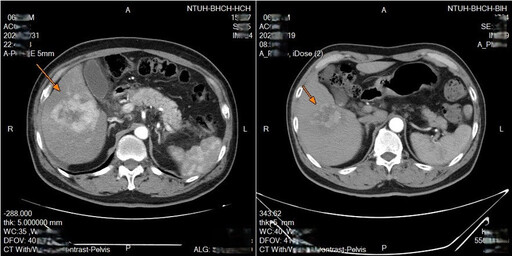

2025-10-29 20:21:56 | 周刊王【今傳媒/記者李祖東報導】74歲張先生日前因腹痛、解黑便至高…

2025-10-29 11:36:03 | 中央社74歲張先生日前因腹痛、解黑便至高醫岡山醫院就醫,意外接連發…